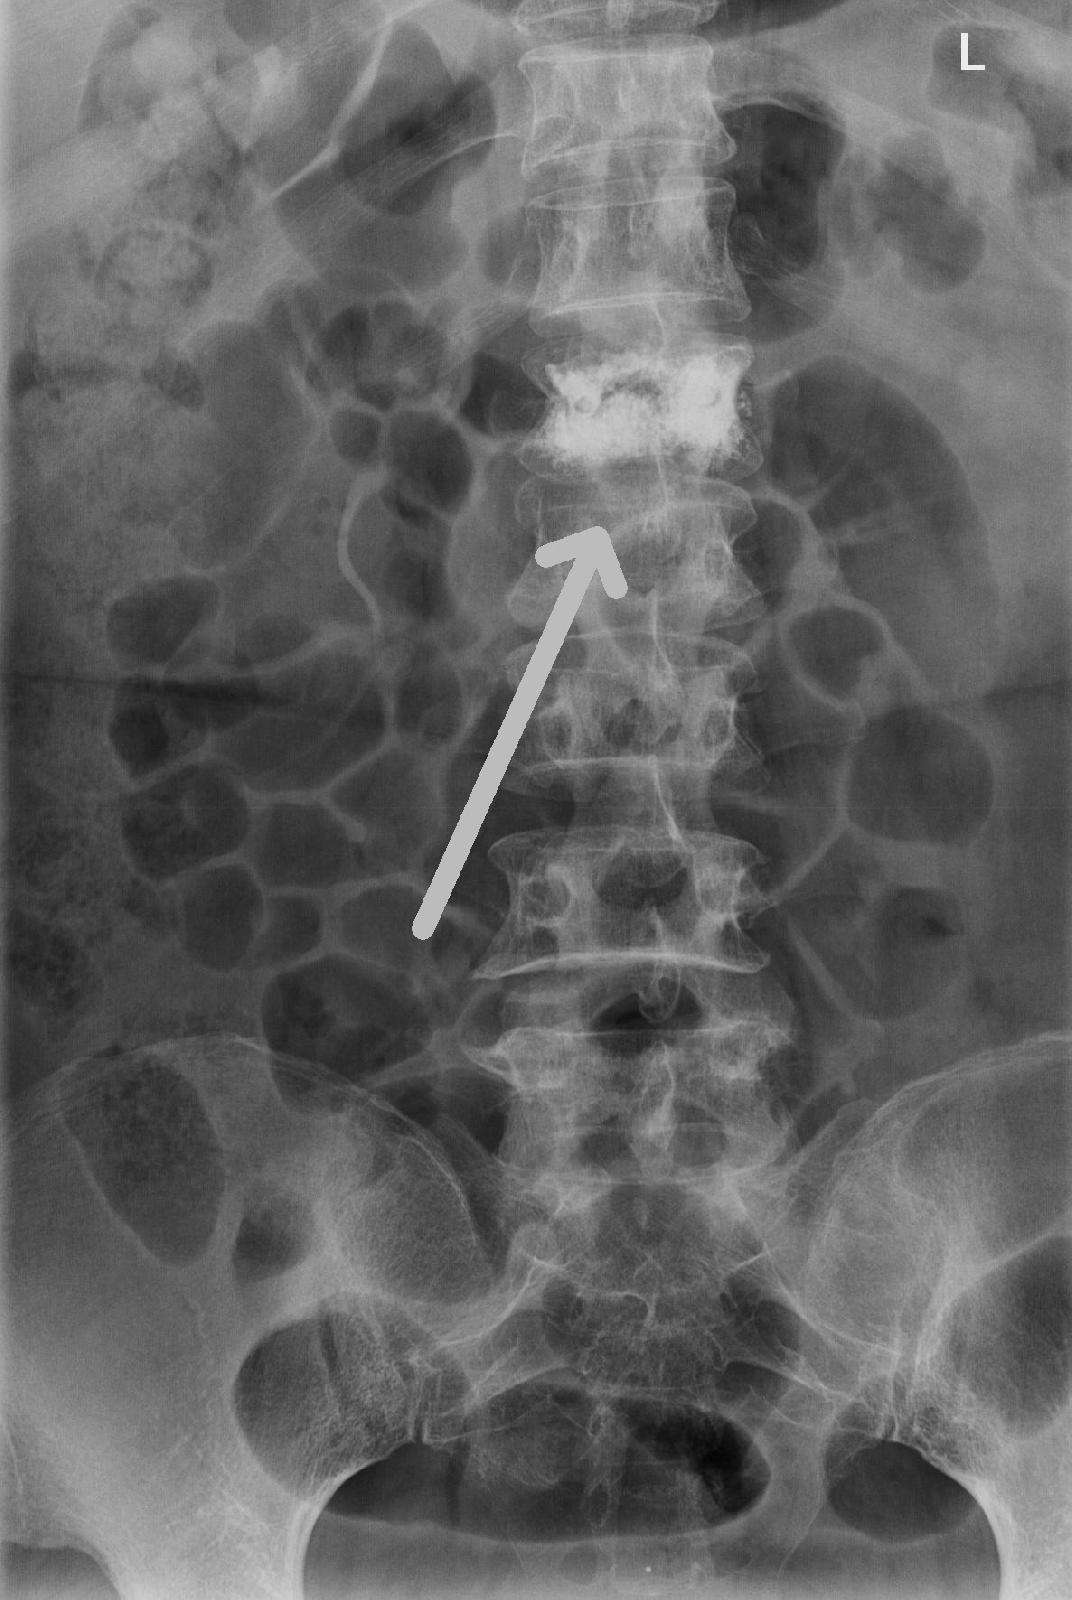

腰1椎体爆裂性骨折,腰1 2 3双侧横突骨折

术前dr示腰1椎体压缩骨折